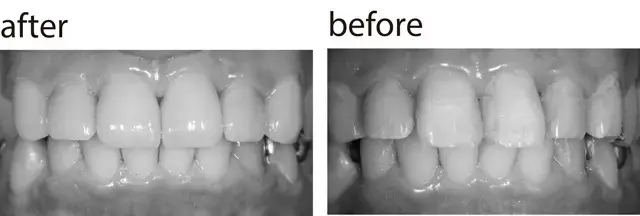

さし歯の歯茎の境目から、歯の根元が見える上のさし歯をセラミッククラウンに。天然歯のよう